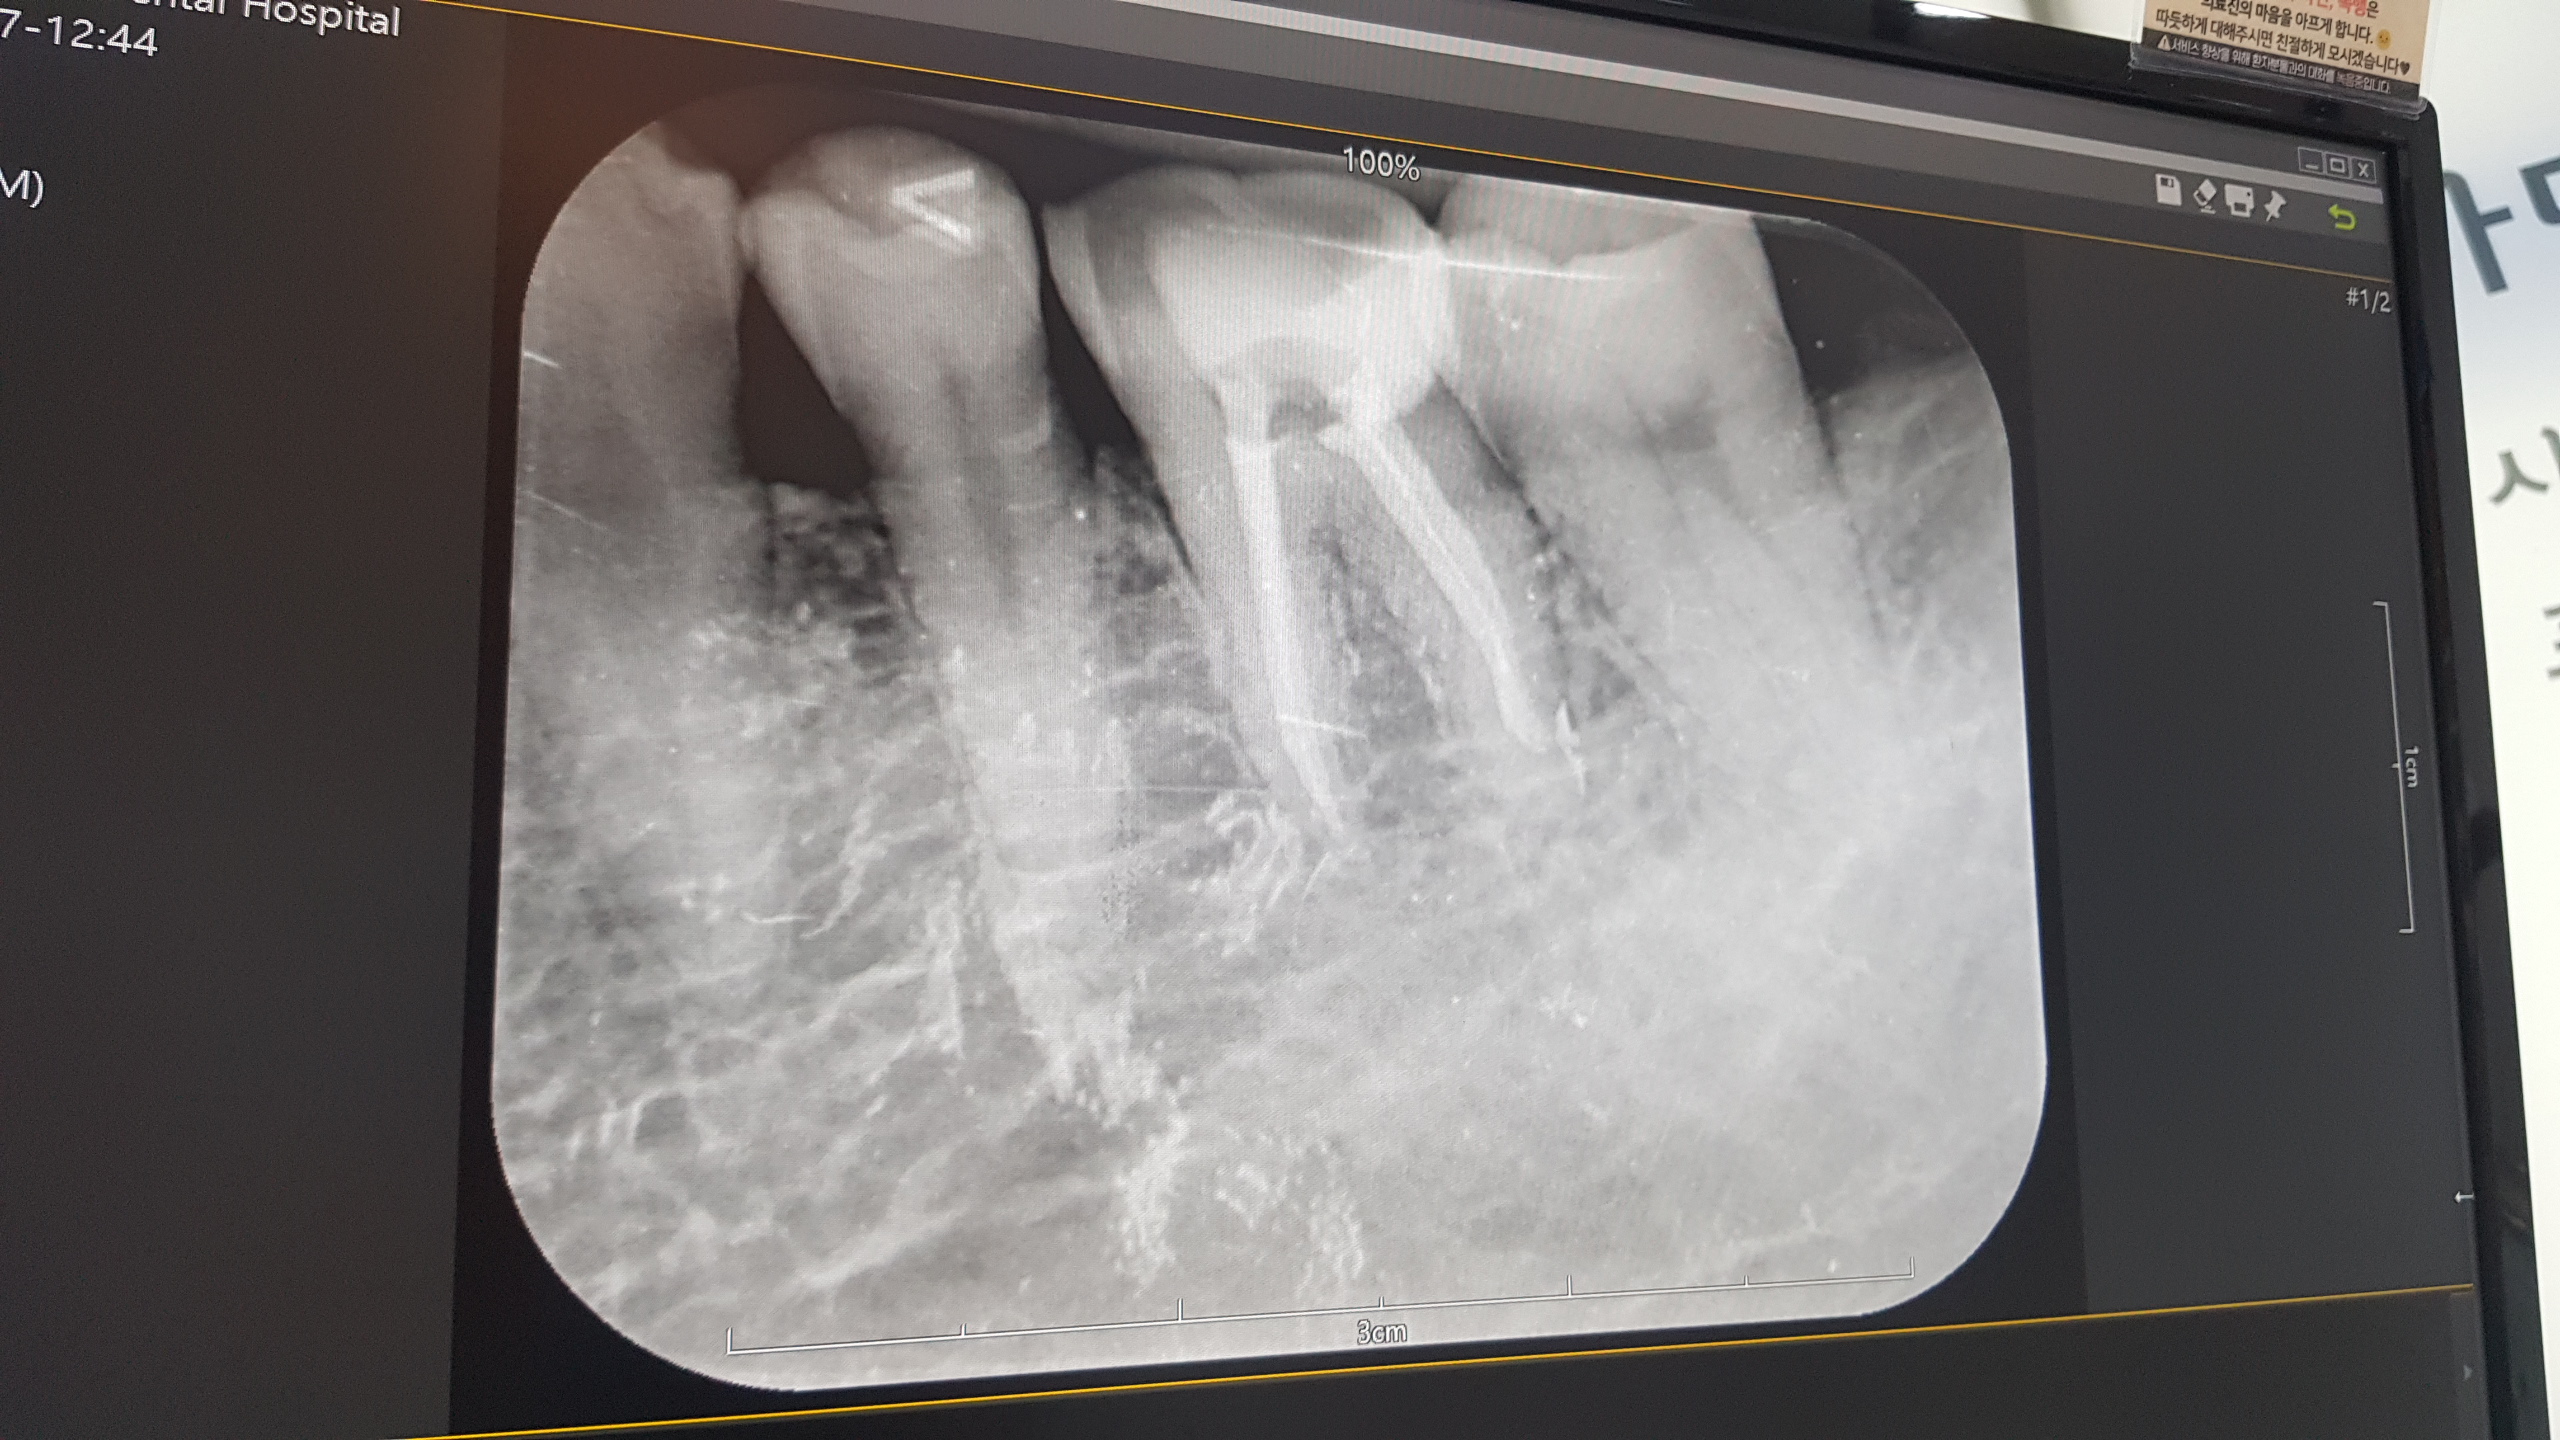

엑스레이를 찍었다..

치료가 잘되었다고..설명해 줍니다..

오늘 치료내용은

신경치료한 곳..신경을 죽인 이빨속을 소독하고,

친환경? 무엇인가를 집어넣고..

똑같이 임시로 마감을 하였습니다.